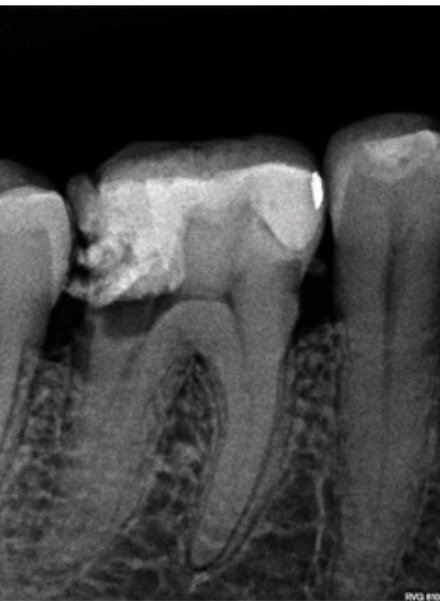

This case used the Bassi Logic 30/.05.

Xrays & Photos: